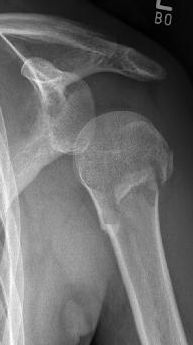

Picture: A subcapital upper arm fracture was treated with a prosthesis. The humeral head was completely removed and replaced by the prosthesis. This is anchored in the upper arm with the prosthesis shaft.